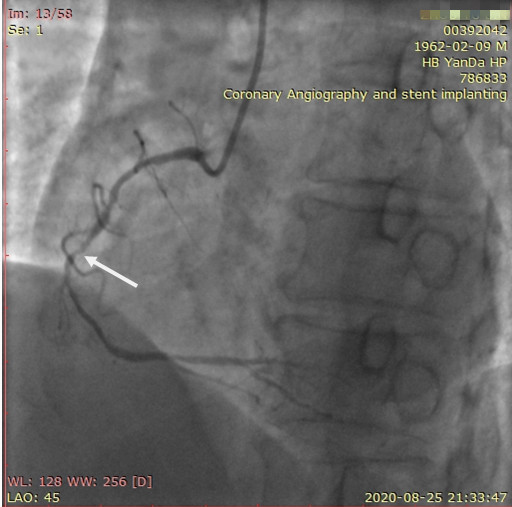

李先生右冠術前影像

李先生右冠術后影像

術前,翟光耀主任還親自為李先生復查冠狀動脈造影,造影結果顯示:患者的前降支、回旋支、右冠等冠脈三支嚴重病變、嚴重鈣化,且均為彌漫性長病變,最重處99%以上管腔極嚴重狹窄。翟主任仔細閱讀造影結果后指出:結合李先生的實際情況,雖然微創介入手術難度比較大,但仍可行;李先生心臟三支主干動脈均存在極其嚴重的狹窄,每一支動脈均至少植入2-3枚支架,根據患者的耐受情況,李先生可能需要分3次分別對三支動脈進行介入手術;考慮到李先生路途遙遠,病情嚴重,不宜反復奔波,并且患者迫切要求能夠徹 底解決病痛,在病情允許的情況下,如果手術順利,爭取為患者進行“一站式”手術,一 次 性解決全部三支動脈病變!

手術方案確定之后,在心血管內三科趙景新主任、介入醫學科富孝晨主任的配合下,翟光耀主任親自擔任主刀,分別依次對李先生的三支動脈進行了完全血運重建。由于手術進展順利,李先生術中沒有任何癥狀,耐受良好,于是成功的將三支動脈“一站式”治療!術中,由于李先生左主干遠端分叉處存在嚴重病變,翟光耀主任選擇國際指南推薦的DK-mini-Crush技術,確保了分叉處兩支主干開口均萬無一失。據悉,DK-mini-Crush技術是目前冠脈分叉病變領域最為復雜及難以掌握的介入技術之一,對手術醫生經驗、體力均提出了極大的挑戰。極為擅長復雜介入技術的翟光耀主任卻用嫻熟的技術確保了李先生手術的成功。

冠狀動脈嚴重鈣化合并狹窄病變是冠脈介入的一大難題,血運重建難度大,成功率低,并發癥發生率高,該例患者的成功救治標志著我院冠脈介入水平又躍上了一個新的臺階。